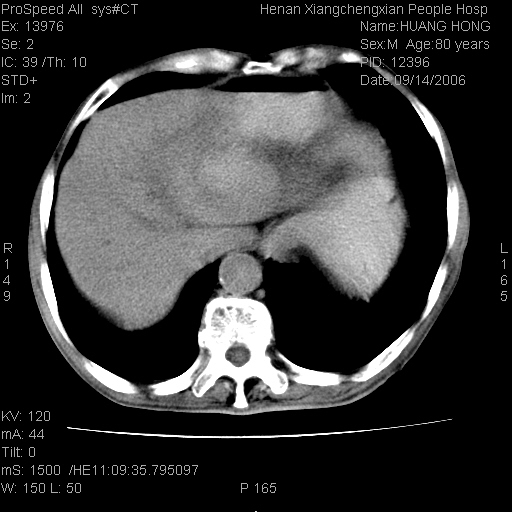

患者, 男, 80岁, 发现上腹部包块1年余,无其它不适.2006-9-14ct片是喝水后扫描2006-9-15ct片没喝水扫描![]() ![]() ![]() ![]() ![]() ![]() ![]() ![]() ![]() ![]() ![]() ![]() ![]() ![]() ![]() ![]() 以上是喝水片 以下是空腹片 ![]() ![]() ![]() ![]() ![]() ![]() ![]() ![]() ![]() ![]() ![]() ![]() ct:胰腺前方、肝脏与胃之间可见巨大类圆形囊性低密度影,大小约152mmx145mmx118mm,上缘平t11椎体上缘,下缘平l3椎体下缘,密度均匀,ct值15hu,其内呈多房分隔,囊壁薄且光滑,边界清晰,周围组织及器官明显受压。肝脏实质内未见异常密度影,胆囊未见异常,胰腺密度未见异常,脾脏大小、形态及密度未见异常,腹膜后间隙未见肿大淋巴结影。 印象:胰腺前方、肝脏与胃之间巨大类圆形囊性低密度影.性质待定。多考虑:.肠系膜巨大囊肿。 守望可可西里发言:支持楼主,考虑肠系膜囊肿,多为小肠系膜。 ysxyy发言:我总觉得这个病人虽然很像肠系膜囊肿,但还是应该强化一下; 下面这几幅图里肿块和主动脉的关系不太清,不知能否除外血管性来源? ![]() ![]() ![]() 病理结果:横结肠系膜间叶瘤.部分区域间质细胞增生活跃. 病理图片 ![]() 良性间叶瘤:是指由两种或两种以上的间叶组织所构成的混合性肿瘤.肿瘤仅发生在腹膜后和肠系膜,.前者较后者多发.良性间叶瘤常发生在肾或四肢,腹膜后较少见,各年龄均可发病.女多与男,预后较好,但术后易复法. 恶性间叶瘤:由两种以上恶性间叶组织成分组成. 光镜:肿瘤由脂肪/血管/平滑肌构成. 原贴地址: http://www.radinet.com.cn/forum_view.asp?forum_id=4&view_id=16217 ok |